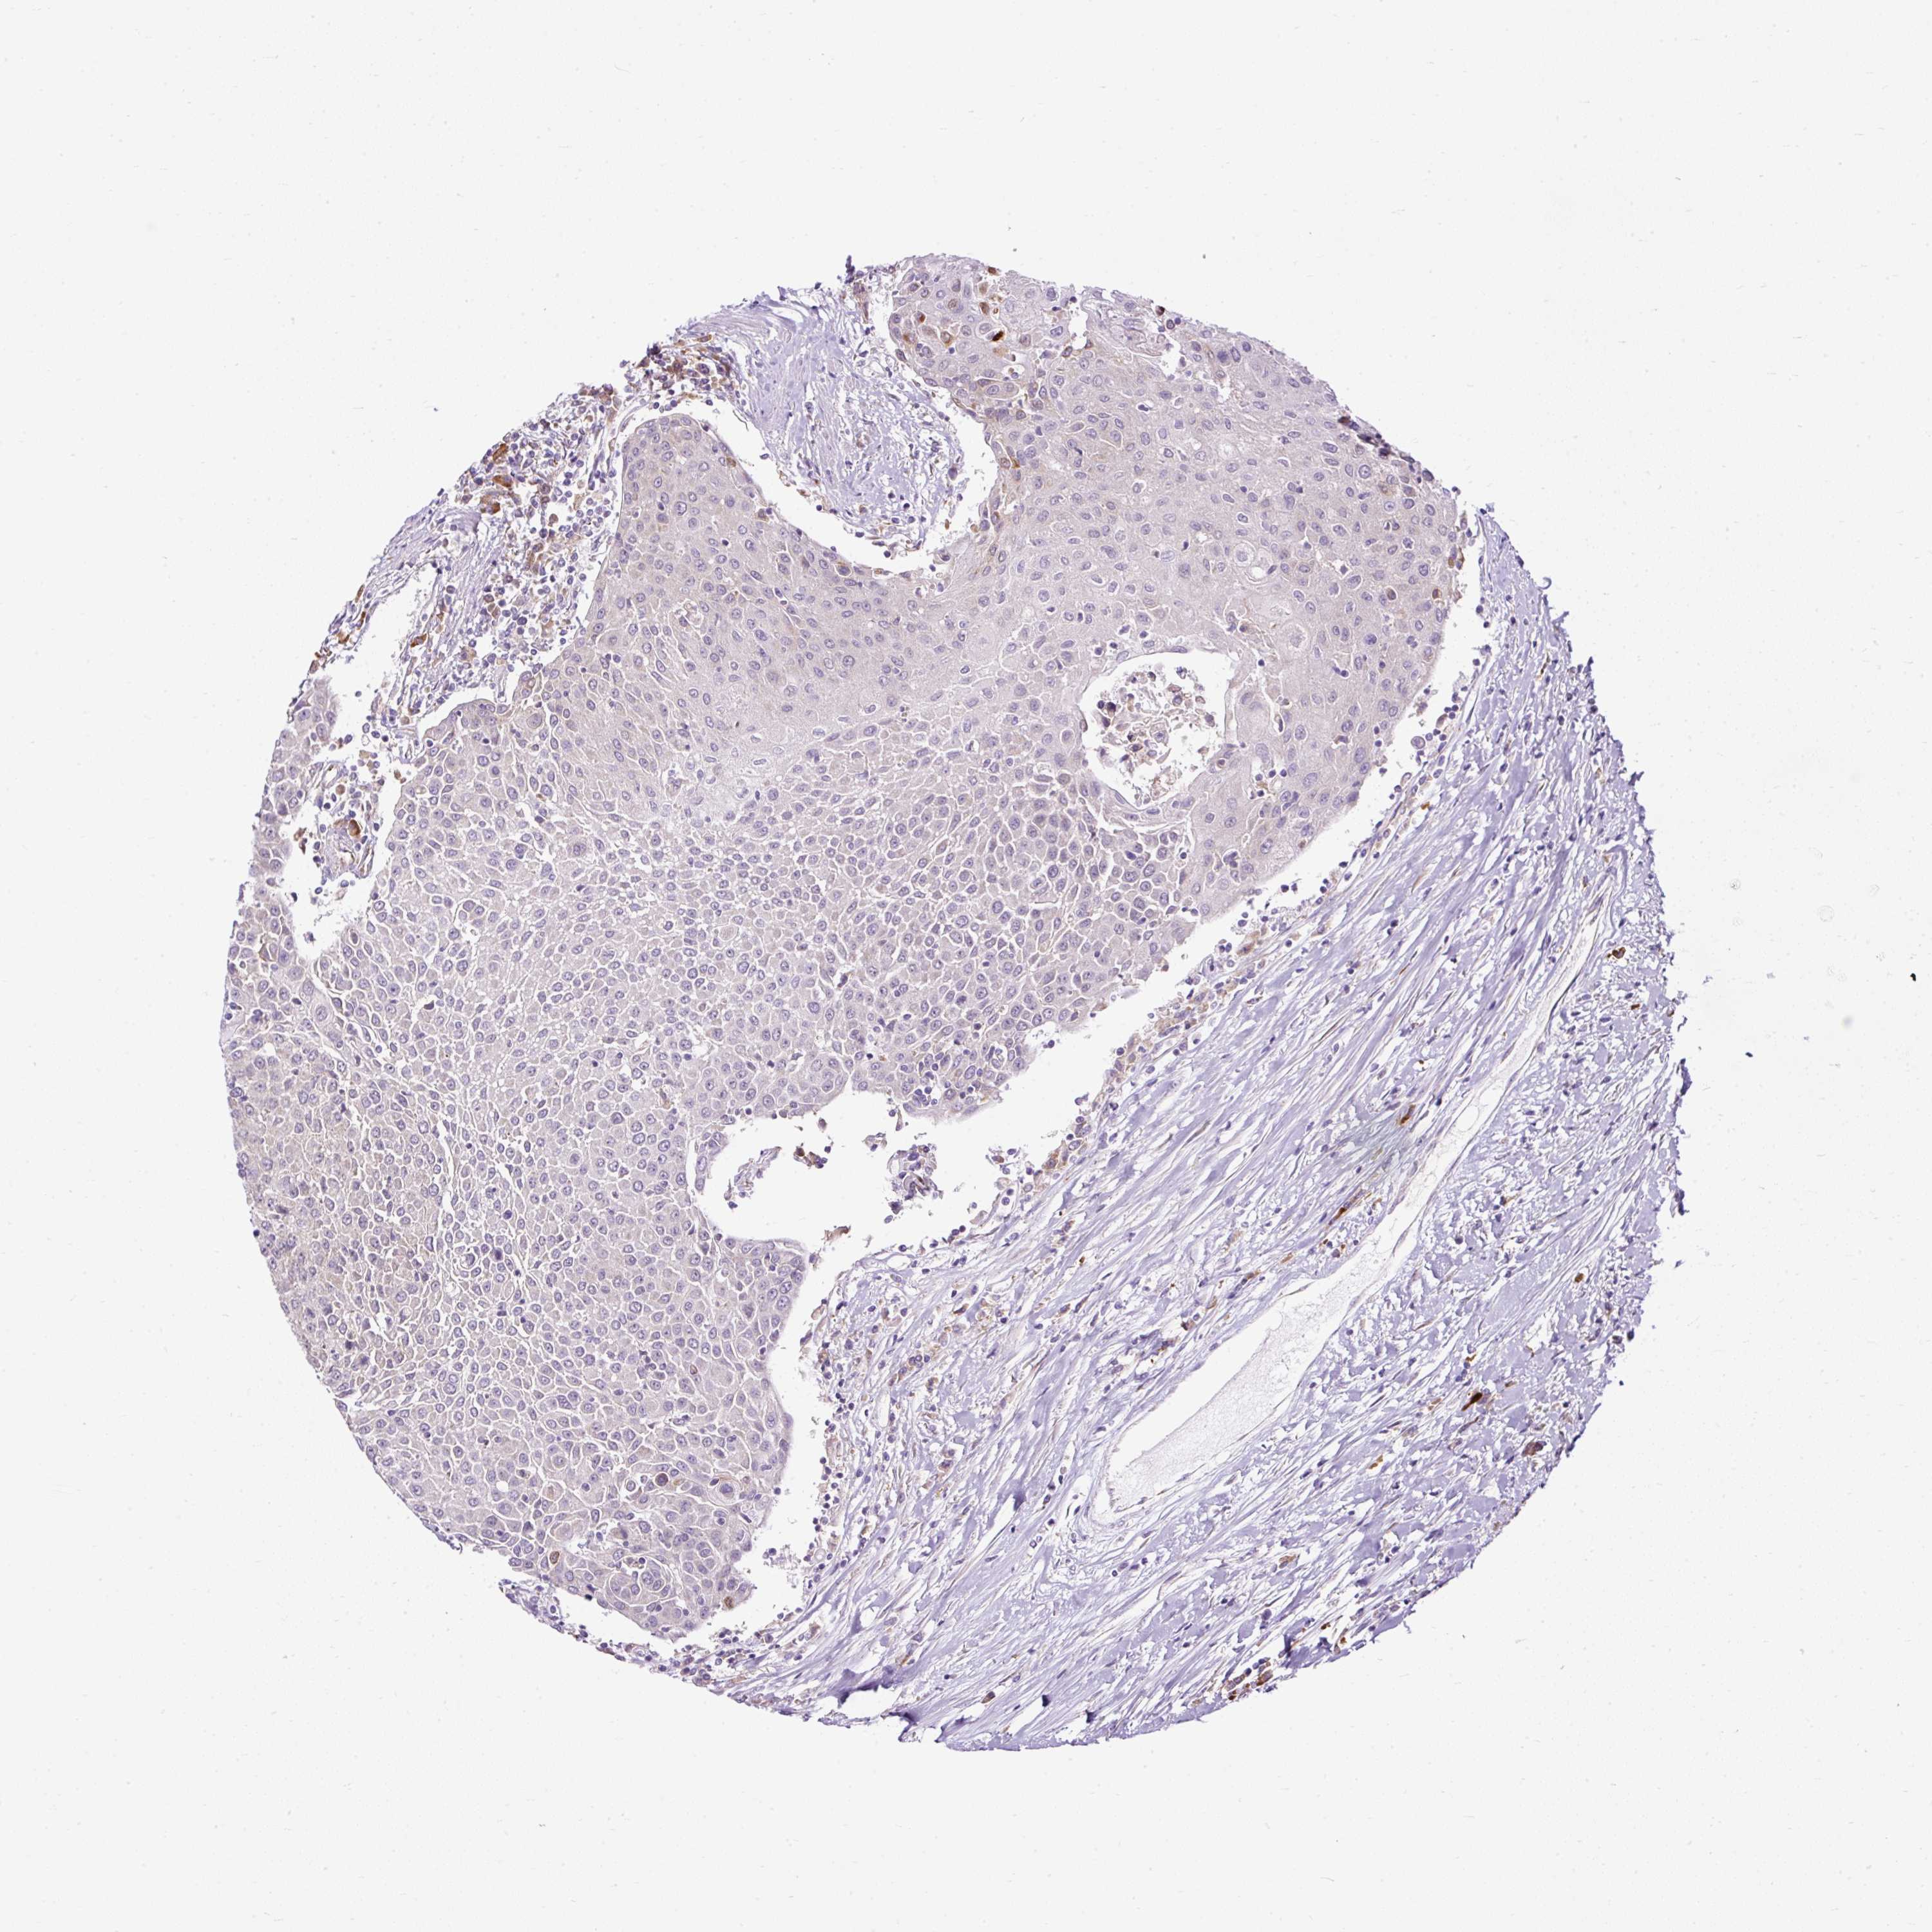

UROTHELIAL CANCER - Protein expressioni

A mouse-over function shows sample information and annotation data. Click on an image to view it in a full screen mode. Samples can be filtered based on level of antibody staining by selecting one or several of the following categories: high, medium, low and not detected. The assay and annotation is described here.

Note that samples used for immunohistochemistry by the Human Protein Atlas do not correspond to samples in the TCGA dataset.

Antibody stainingi

Antibody staining in the annotated cell types in the current human tissue is reported as not detected, low, medium, or high, based on conventional immunohistochemistry profiling in selected tissues. This score is based on the combination of the staining intensity and fraction of stained cells.

Each image is clickable and will lead to virtual microscopy that enables deeper exploration of all samples and also displays staining intensity scores, fraction scores and subcellular localization as well as patient and tissue information for each sample.

Antibody HPA045663

Antibody HPA051631

Urothelial carcinoma, High grade

Urothelial carcinoma, NOS

Urothelial carcinoma, Low grade